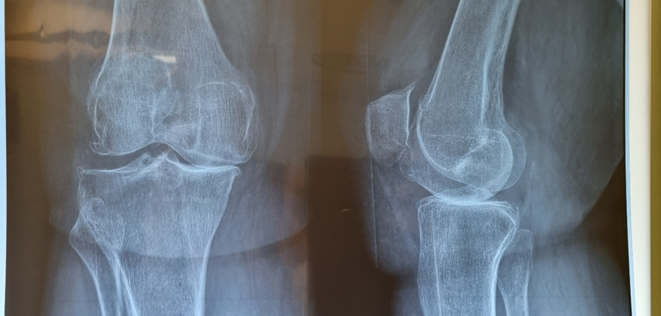

- Ασθενής: Γυναίκα 72 ετών με σοβαρή οστεοαρθρίτιδα γόνατος.

- Προεγχειρητικά: Λεπτομερής ακτινολογική αξιολόγηση.

Προεγχειρητική ακτονογραφία